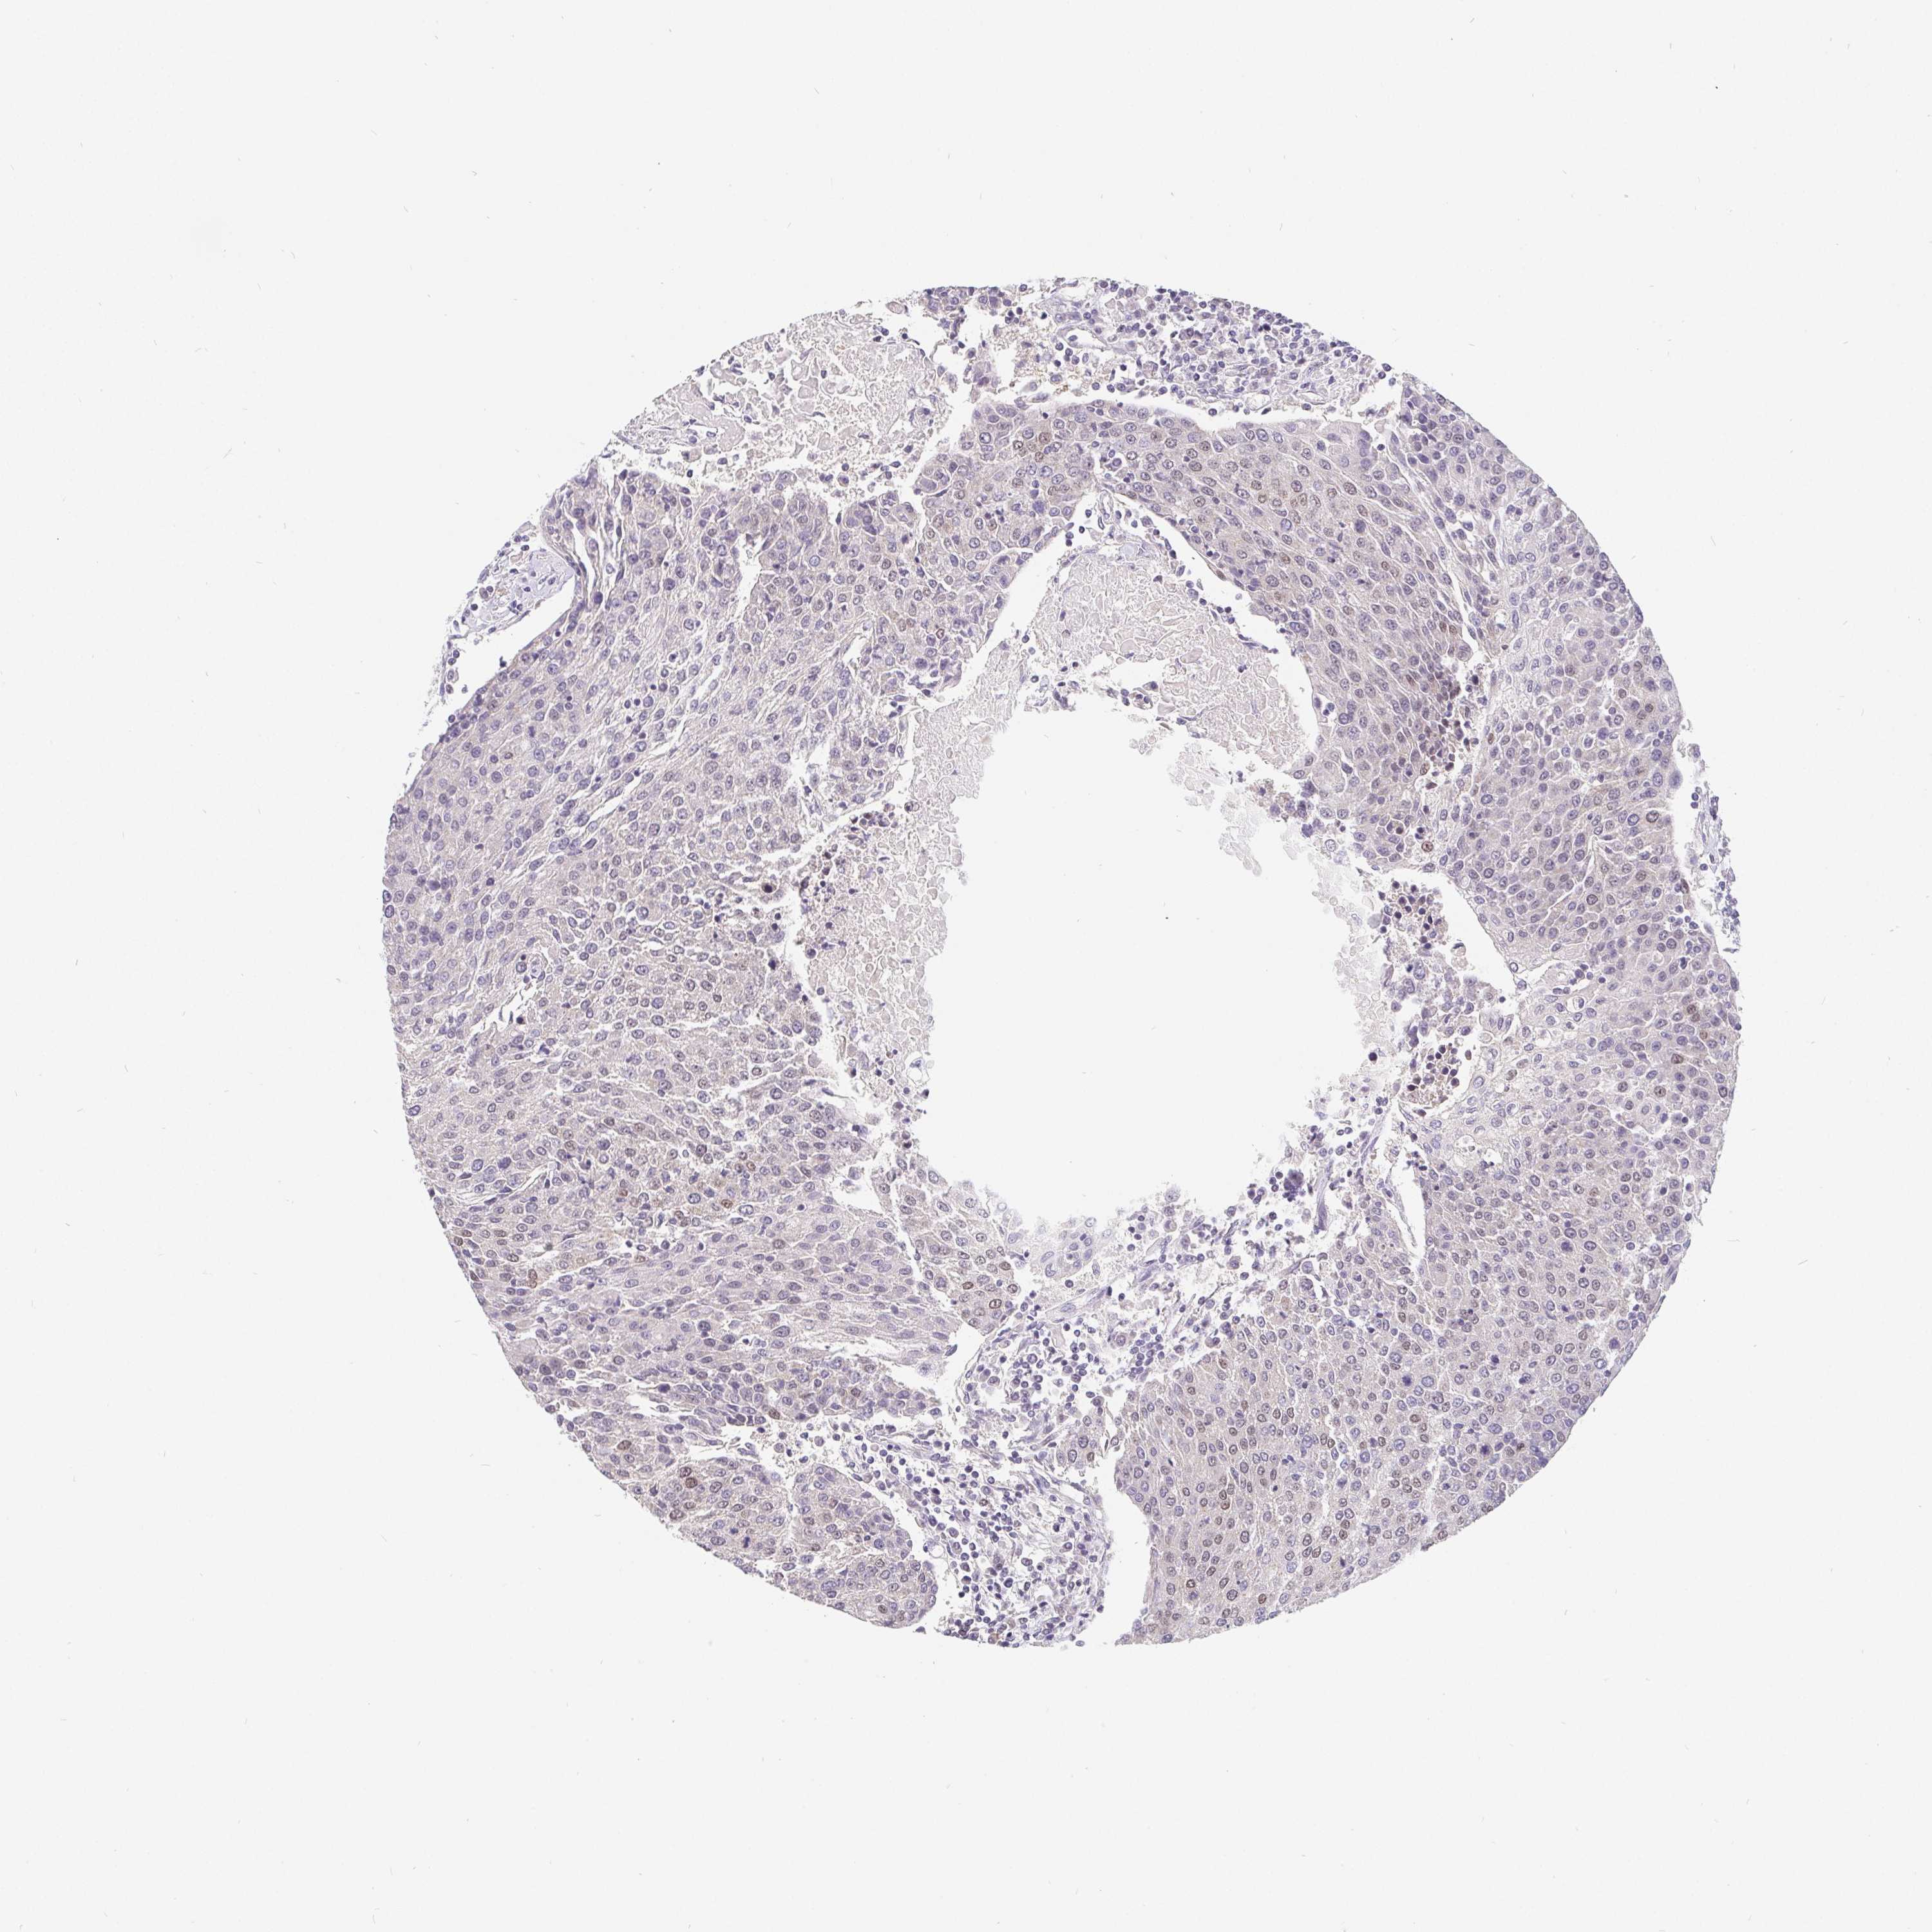

UROTHELIAL CANCER - Protein expressioni

A mouse-over function shows sample information and annotation data. Click on an image to view it in a full screen mode. Samples can be filtered based on level of antibody staining by selecting one or several of the following categories: high, medium, low and not detected. The assay and annotation is described here.

Note that samples used for immunohistochemistry by the Human Protein Atlas do not correspond to samples in the TCGA dataset.

Antibody stainingi

Antibody staining in the annotated cell types in the current human tissue is reported as not detected, low, medium, or high, based on conventional immunohistochemistry profiling in selected tissues. This score is based on the combination of the staining intensity and fraction of stained cells.

Each image is clickable and will lead to virtual microscopy that enables deeper exploration of all samples and also displays staining intensity scores, fraction scores and subcellular localization as well as patient and tissue information for each sample.

Antibody HPA064323

Antibody CAB002608

Urothelial carcinoma, High grade

Urothelial carcinoma, NOS

Urothelial carcinoma, Low grade

Adenocarcinoma, NOS